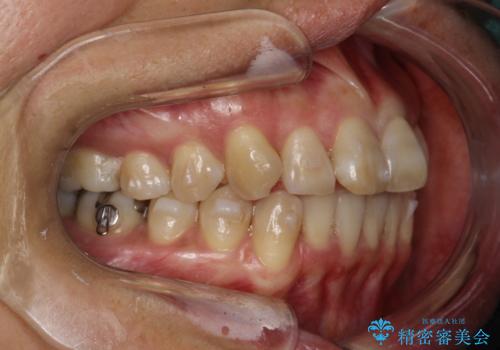

- 上下の歯並びにガタつきがあり、また、上下前歯の前後のズレが大きく上の前歯が突出しています。

インビザラインではガタつき(叢生)の改善だけでなく、上下の前後的なズレについてもアプローチが可能です。

インビザラインの特色を生かした歯牙移動計画を作成し、非抜歯にて治療を行いました。

上の歯列に後方への力をかけるために、患者様には顎間ゴムをマウスピースと共に併用してもらいました。